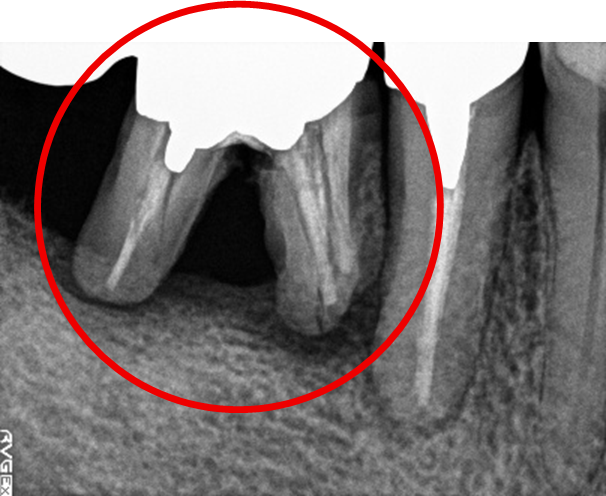

右下奥の歯が、グラグラして噛むと痛い。

治療内容

歯根の周りの骨が全く無い状態でしたので、保存することができず抜歯しました。3本歯がないところに2本インプラントを埋入しました。

Before

※赤丸を抜歯しました。

After